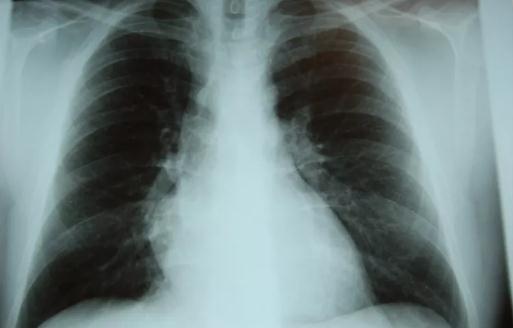

发现肺结节后最重要的一件事是排除肺癌。/ quanjing